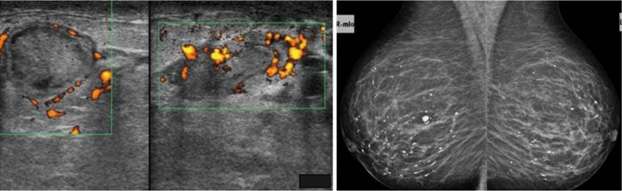

Periductal mastitis is histopathologically defined as a chronic inflammatory condition of the major mammary ducts, with associated duct ectasia and plasma cell infiltration. It is usually seen in reproductive-age women. The cause and pathophysiology is not entirely understood. However, smoking appears to play a role in the development of this condition, either causing direct or indirect damage to the epithelial lining of the milk ducts, leading to inflammation, sloughing of epithelial cells, plugging and dilation of the duct and subsequent infection. Bacteria have also been implicated in the pathophysiology, with isolated organisms including Staphylococcus aureus, Enterococcus, Pseudomonas, Bacteroides, and Proteus species. Clinical symptoms include a subareolar mass with or without associated pain, erythema, nipple discharge, and/or nipple inversion. Imaging features on mammography include characteristic thick, linear, cigar-shaped or rod-like calcifications, with the long axis pointing toward the nipple. These calcifications tend to be longer, thicker, and smoother than calcifications seen with DCIS or ductal carcinoma. Sonographic features typically include dilated intramammary ducts with internal echogenic filling defects and increased surrounding vascularity. Complications are similar to lactational mastitis and include abscess and fistula formation.